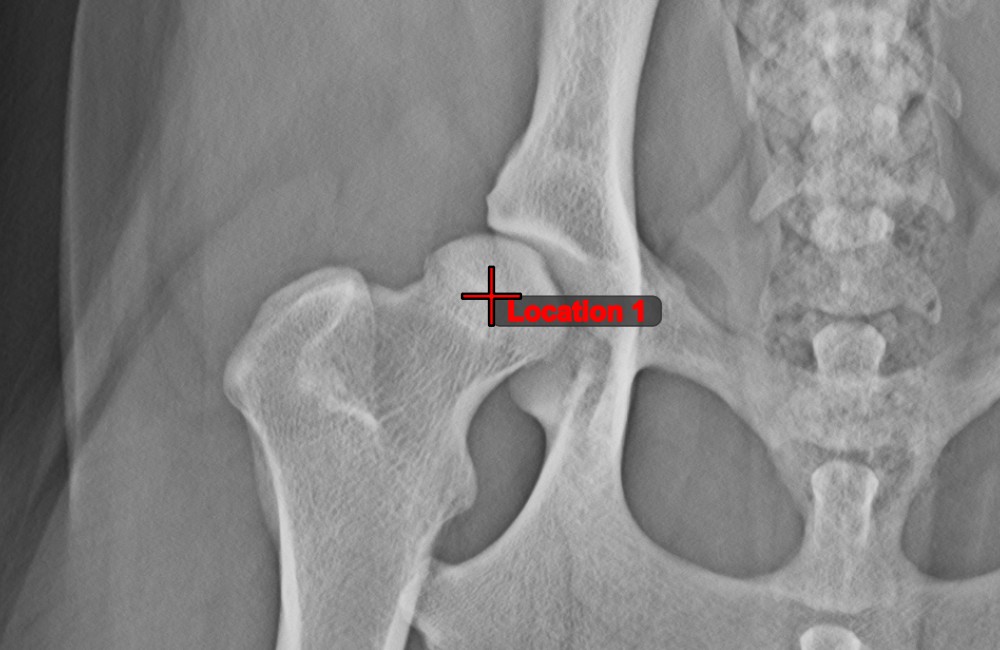

Text Tool¶

Label and comment important information on the image by using the Text Tool. The text is always assigned to a point that can be later modified by using the Select/Move Item tool.